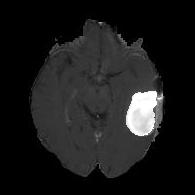

(a) (b) (c) (d)

Boundary Stream:

Fig. 2 demonstrates the output of each of the attention layers in our dedicated boundary stream. In essence, each attention layer progressively localizes the tumor and refines the boundaries. The first attention layer has learned rough estimate of the boundaries around the tumor and localized it, whereas the second and third layers have learned more fine-grained details of the edges and boundaries, refining the localization. Moreover, since our architecture leverages a dilated spatial pyramid pooling to merge the learned feature maps of the regular segmentation stream and the boundary stream, multiscale regional and boundary information have been preserved and fused properly, which has enabled our network to capture the small structural details of the tumor.